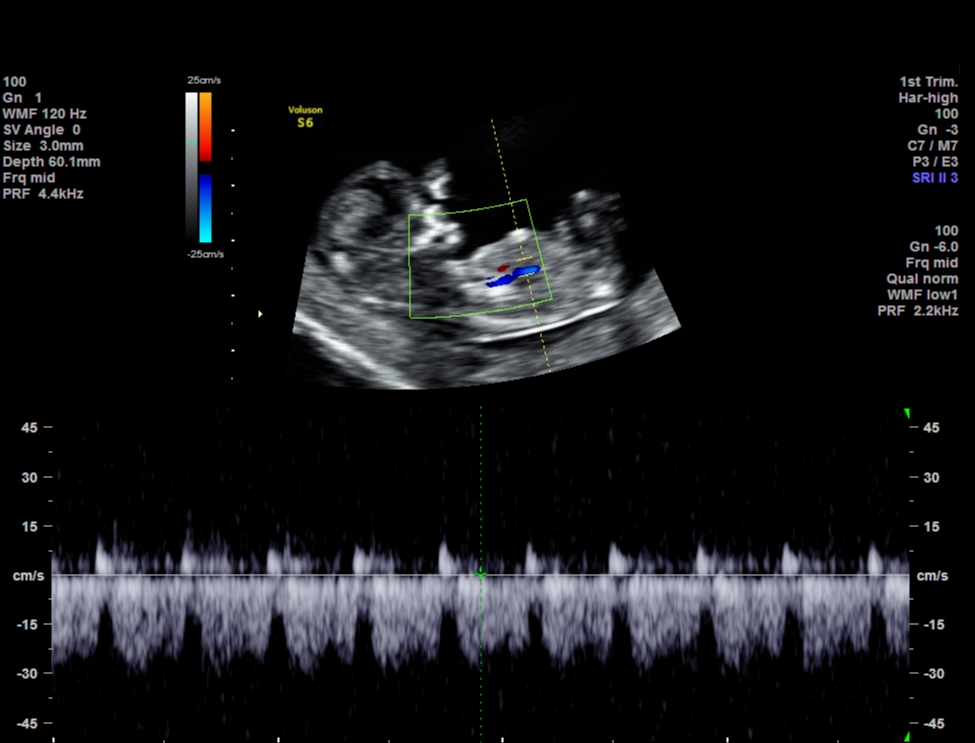

Attachment 33524

HI everyone, This is my 1st post in this forum after reading many threads about gender predictions and some of you ladies are very knowledgable. These are my NT scan pics for today.

One picture I asked tech what the gender is and she said she was very unsure but it might develop to girl part. What do you guys think? I googled some boys potty shot also has three lines and why mine is protruding ???